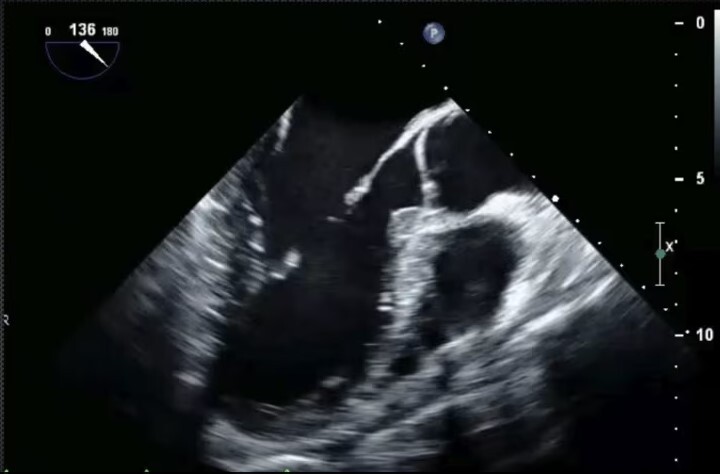

Mid-Esophageal Long Axis View. Multiplane to between 120-140 degrees. Center LVOT. Structures: L atrium, L ventricle, LVOT, aortic valve, R ventricle, posterior & anterior leaflets of mitral valve.